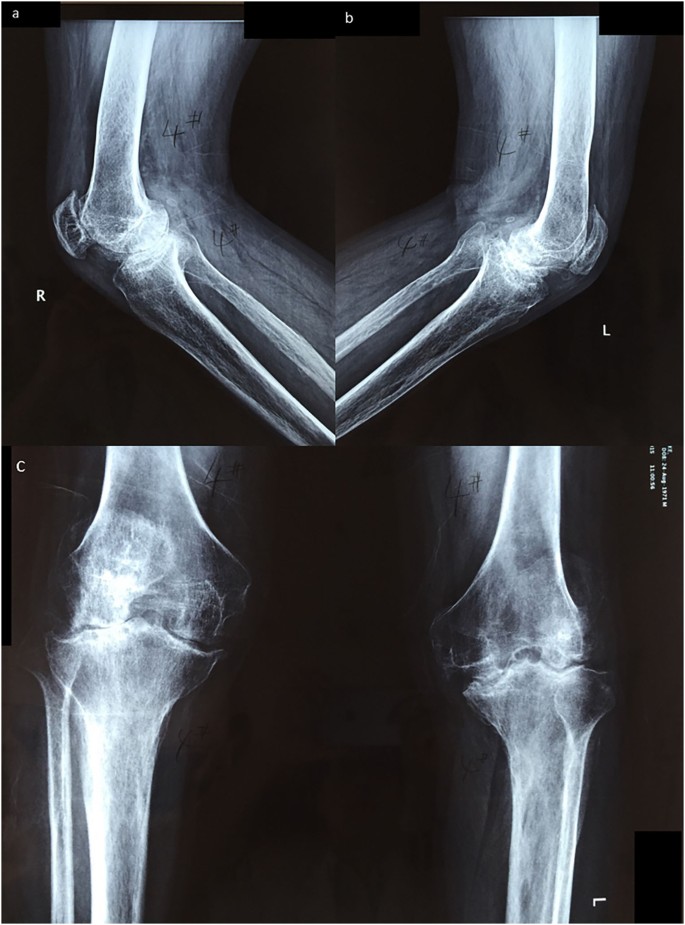

End Stage Bilateral Knee Osteoarthritis

Not A Typical Case Of Bilateral Knee Osteoarthritis The Bmj